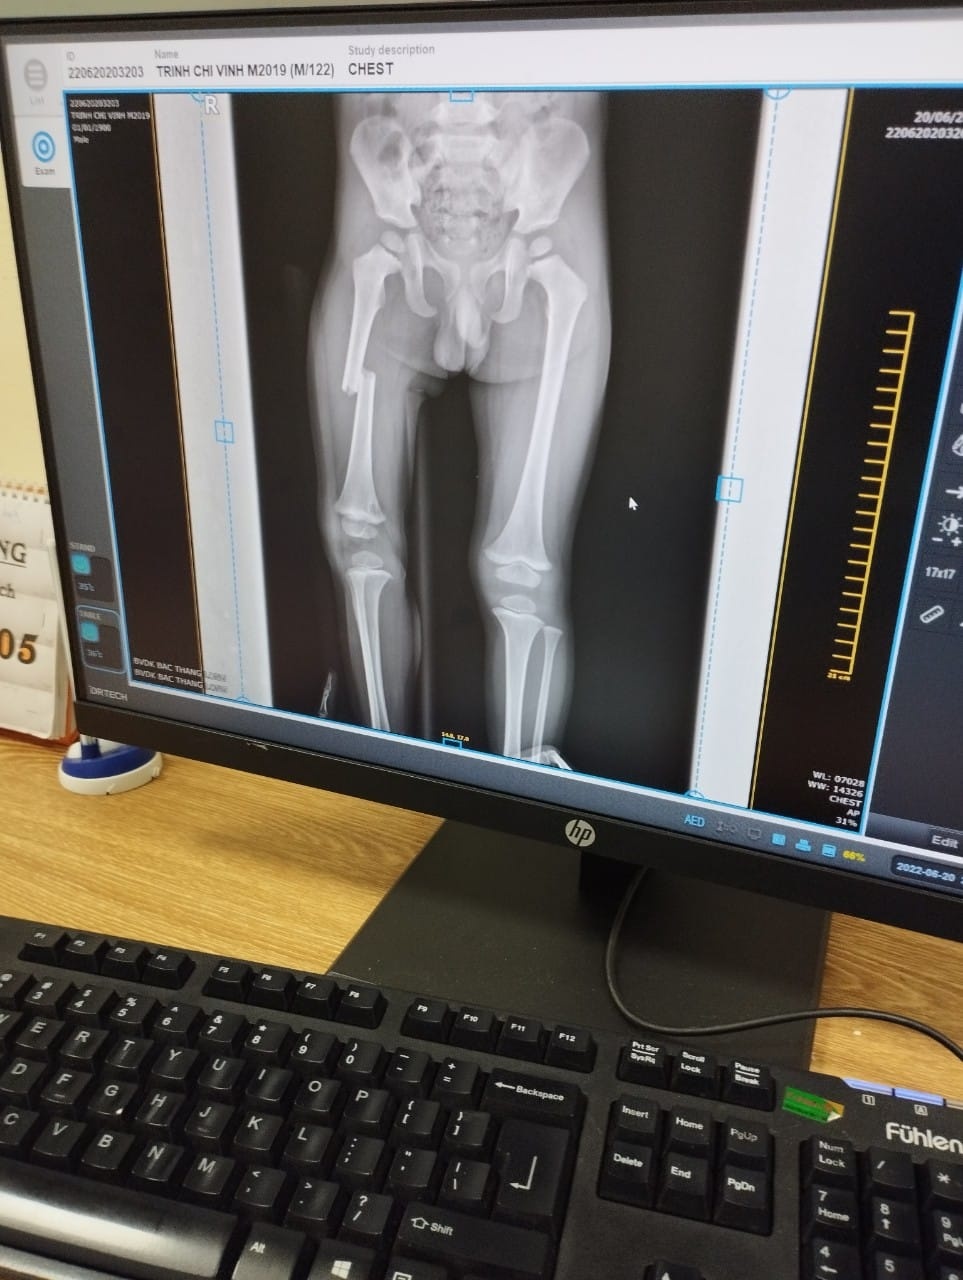

Ảnh chụp cho thấy bé trai bị gãy xương đùi phải. Ảnh: Gia đình cung cấp.